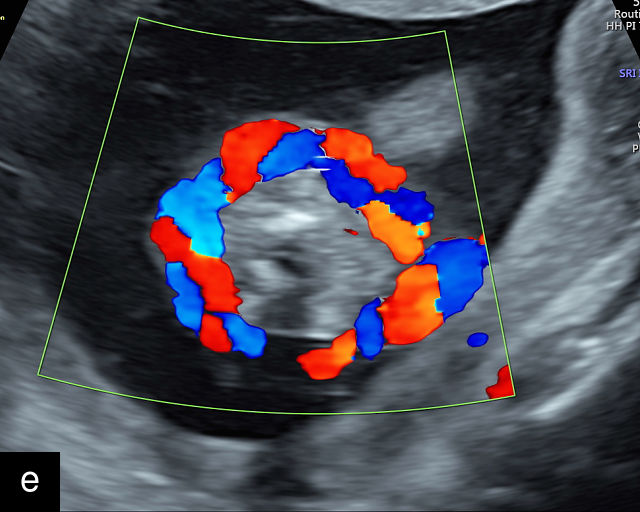

Placental chorioangiomas

Chorioangiomas are benign tumors of the placenta, arising from chorionic tissue.141 These tumors consist of capillaries and cellular stroma in varying proportions.141,142 While clinical diagnosis of chorioangiomas is relatively uncommon, histopathological analysis reveals their presence in approximately 1% of all placentas.142 Most chorioangiomas identified on prenatal ultrasound are incidental findings during routine examination and are typically those that are larger in size.9 Consequently, the prevalence of chorioangiomas detected sonographically is significantly lower than the prevalence observed in pathological examinations of placentas. More rarely, chorioangiomas may be detected during ultrasound evaluation for polyhydramnios or FGR.143 Large chorioangiomas (greater than 4 cm in diameter) are thought to occur in approximately 1 : 3500–1 : 9000 pregnancies (0.01–0.03%).141 These larger chorioangiomas may be associated with significant complications, including polyhydramnios, fetal hydrops, fetal anemia, FGR and even fetal death.9,141,143,144,145 A systematic review reported a fetal death rate of 8.2% in cases of prenatally diagnosed chorioangioma in which no intervention was performed.145 Additionally, preterm birth before 37 weeks occurred in 34.1% of these pregnancies (95% CI, 21.1–48.3%). The study also found that 24.0% of infants (95% CI, 13.5–36.5%) were born small-for-gestational age.145 The most important predictor of outcomes was the size of the tumor.145

The typical sonographic appearance of a chorioangioma on grayscale ultrasound is a well-circumscribed mass arising from the fetal surface of the placenta, protruding into the amniotic cavity, and distinctly separate from the placenta (Figure 12; Video 7). These tumors are most commonly located near the umbilical cord insertion site on the placenta. Sonographically, they may appear hypoechoic or hyperechoic and are often heterogeneous, with possible calcifications, hemorrhage or infarction visible within the mass.9 The appearance of these masses may change over time.141 Color flow Doppler imaging typically reveals vascularity within the tumor, showing low-resistance vessels and arteriovenous shunts (Figure 12c–e; Video 7).9 These shunts are believed to contribute to fetal complications such as high-output cardiac failure, anemia and hydrops.141 Three-dimensional ultrasound may be helpful in assessment of the mass.146 Importantly, the differential diagnosis includes placental hemorrhage, and color flow Doppler is essential to assist in making the diagnosis.

Grayscale (a,b), color Doppler (c,e) and power Doppler (d) images of chorioangiomas, showing heterogeneous masses protruding from the placental surface.

When a chorioangioma is identified on prenatal ultrasound, close fetal surveillance is essential. Initial monitoring includes weekly ultrasound examinations to assess amniotic fluid volume and fetal cardiac function, as polyhydramnios and hydrops can develop rapidly. Polyhydramnios is the most common complication of chorioangioma, complicating between 14% and 28% of cases, and when severe, may lead to maternal discomfort, respiratory embarrassment and preterm labor.141,143,147,148 Fetal growth should be evaluated every 4 weeks. Maternal mirror syndrome, with severe pre-eclampsia has also been described.149,150

Management of complications related to chorioangioma may include interventions such as amnioreduction to manage severe polyhydramnios.149,151 More recently, a variety of fetal surgical procedures have been developed to treat these tumors, with varying degrees of success. Additional interventions include intrauterine fetal transfusion to correct anemia and various fetoscopic techniques to occlude tumor vessels, such as embolization with injection of vascular plugs, and radiofrequency or laser ablation of the feeding vessels.143,144,152,153,154,155,156,157